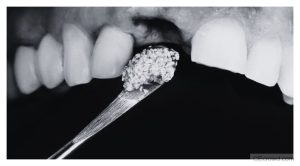

Join us for a live webinar on bone trauma and healing, focusing on the role of biomaterials and bone graft substitutes in surgical practice.